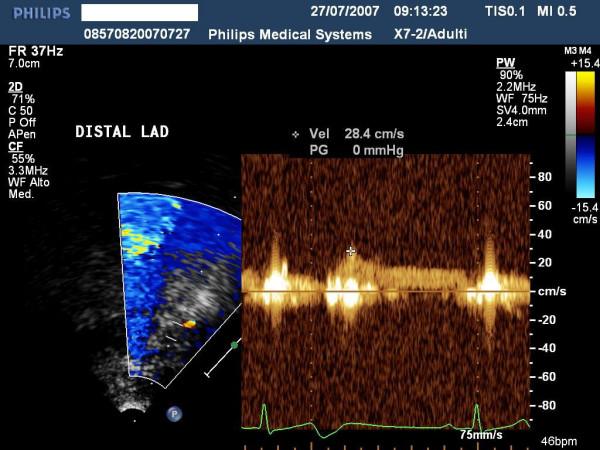

The aim of this paper is to highlight coronary investigation by transthoracic Doppler evaluation. This application has recently been introduced into clinical practice and has received enthusiastic feedback in terms of coronary flow reserve evaluation on left anterior coronary artery disease diagnosis. Such diagnosis represents the most important clinical application but has in itself some limitations regarding anatomical and technological knowledge. The purpose of this paper is to offer a didactic approach on how to investigate the different segments of left anterior and posterior descending coronary arteries by transthoracic ultrasound using different anatomical key structures as markers. We will conclude by underlining that, nowadays, innovative technology allows complete evaluation of both major coronary arteries in many patients in a resting condition as well as during pharmacology stress-tests, but we often do not know it.